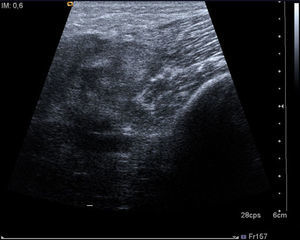

After three days of treatment, the patient persisted with the same symptoms showing no improvement. A soft tissue ultrasound reveled a dysfunctional muscle area in relation with the vastus medialis of quadriceps and the adductors muscles compatible with pyomyositis (Fig. 1). A MRI study confirmed the diagnosis (Fig. 2). Consequently, our department was consulted in order to consider surgical debridement. Finally he was taken to surgery performing a complete debridement and drainage of the muscle injury. Samples were collected and sent for microbiological study, identifying an infection due to E. coli as the causative agent.